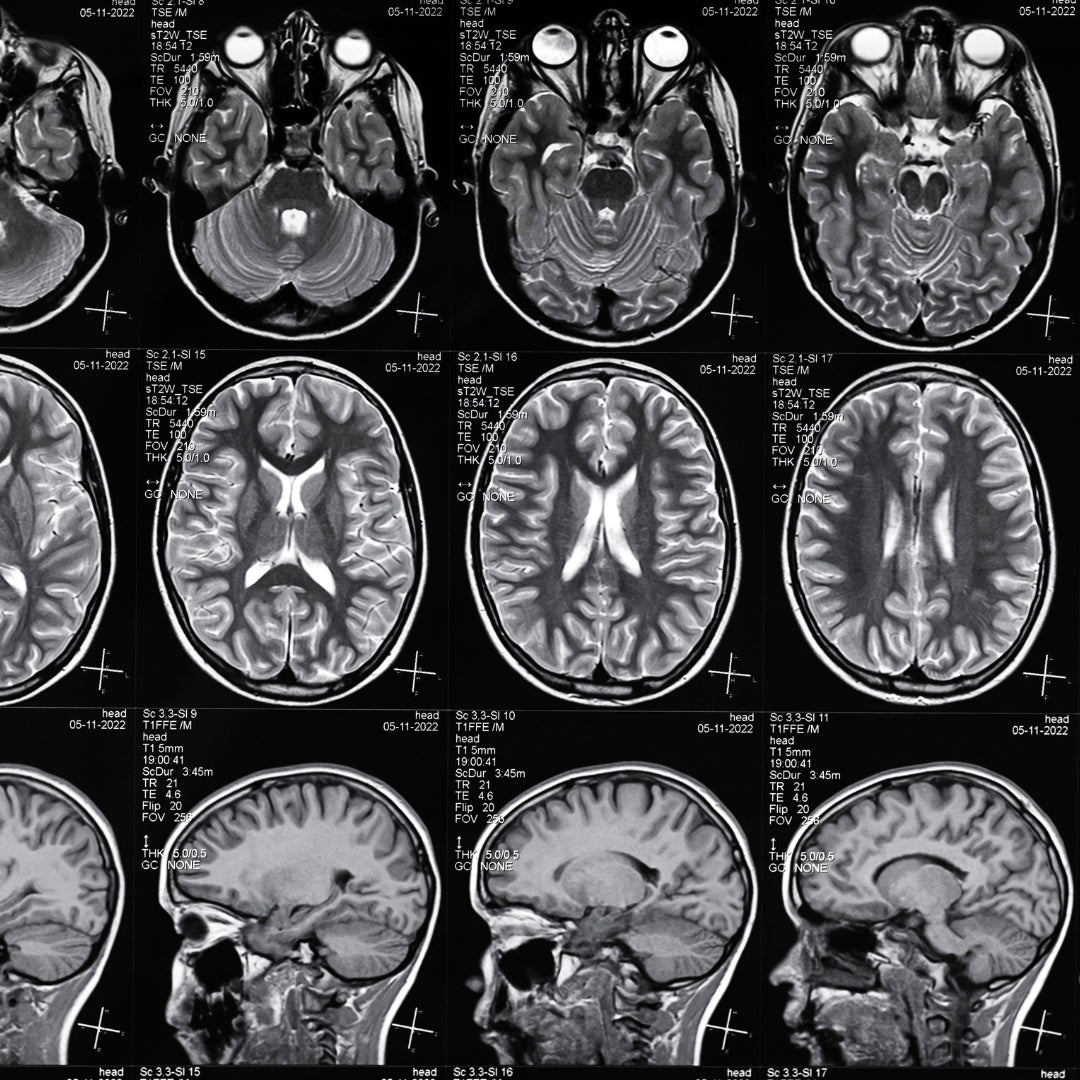

El neurofeedback es una técnica avanzada y no invasiva que permite entrenar al cerebro para mejorar su funcionamiento. Utilizando tecnología de punta, el neurofeedback proporciona retroalimentación en tiempo real sobre la actividad cerebral, ayudando a identificar patrones irregulares y a optimizar su regulación. Este enfoque es cada vez más popular como un tratamiento complementario para una variedad de trastornos emocionales, mentales y físicos.

El proceso de neurofeedback consiste en medir la actividad eléctrica del cerebro a través de sensores colocados en el cuero cabelludo. Estos sensores recogen información que se traduce en gráficos o estímulos visuales y auditivos en una pantalla. A medida que el cerebro recibe esta retroalimentación, aprende a ajustarse para mejorar su rendimiento y equilibrio emocional.